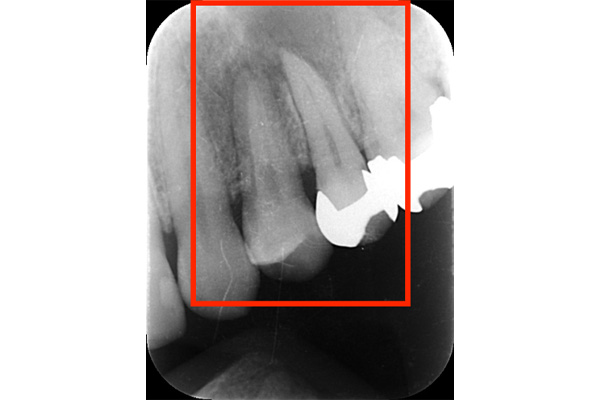

こちらは、歯の根の治療を行い、根の先端までキレイにし、防腐剤をしっかり詰めなおしましたが、膿が溜まったまま治癒しませんでした。破折に気づけなかったのです。

破折に気づいてからは、抜歯を行い、インプラントを入れてまた噛める様にしていきました。レントゲンでも破折がわからない時があります。そんな時はCTやマイクロスコープを使うとわかることが多いのです。